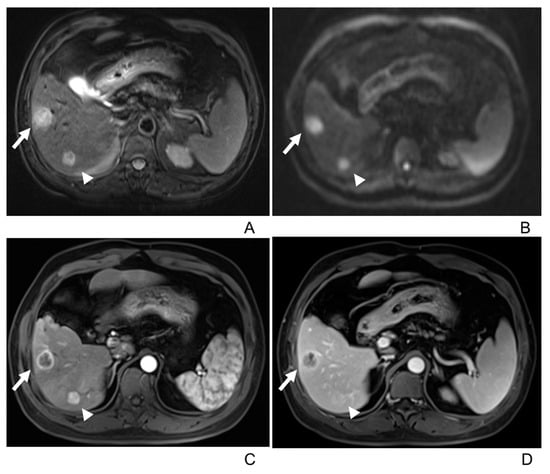

3.2. Imaging Manifestations

- Only two lesions showed a scar-like enhancement in the tumor in AP.

- Two tumors had associated satellite lesions.

- Four patients had portal vein tumor thrombosis (Figure 3).

- Three patients exhibited intrahepatic biliary dilation, and one patient had distal metastasis on the 12th rib (Figure 3).

- Furthermore, lymph node enlargement was found in 9 patients, and metastases were discovered pathologically in 11 patients. The median short-axial diameter of the lymph node was 2.1 cm (range, 0.7 cm to 2.9 cm). Only two lymph nodes had necrosis inside, while the others all showed homogeneous hypervascular enhancement.

- Two patients underwent the gadoxetic acid-enhanced MRI, and both tumors showed hypointense in the hepatobiliary phase.